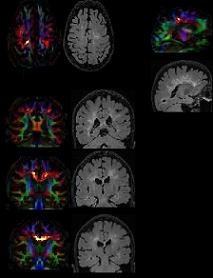

A 20 CPU rack-mounted computing cluster is installed in a dedicated server room in the Mellen Center MRI Laboratory at Cleveland Clinic. This equipment consists of five nodes with double dual-core CPU units (1 Dell PowerEdge 2950 + 4 Dell PowerEdge 1950). Each unit has 4 GB of RAM and 1.5 TB of disk space. This system is connected via a dedicated 1Gb/s CAT 6 ethernet line to the image analysis laboratory cluster described above. This system is available for CPU-intensive applications that are distributable over many processors simultaneously such as DTI post-processing and MR image reconstruction.

The dedicated research 3 Tesla MR imaging facility at the Mellen Center is utilized for a wide range of MRI imaging studies. Facilities include laboratory space, fabrication facilities, high-end computing and data analysis equipment and software, as well as a state-of-the-art 3 Tesla Siemens Tim Trio MR system.

The laboratory provides advanced radiographic data manipulation services to both radiologists and clinicians of Cleveland Clinic and referring institutions, supporting the section's mission by maximizing diagnostic yield of CT and MR data sets and by optimizing staff radiologist workflow. The Lab processes neurovascular, coronary, abdominal and peripheral endovascular CT data, generating pre-rendered surface-shaded display and MIP data, as well as brain perfusion maps from both CT and MR data sets.